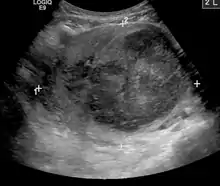

| A very large (9 cm) fibroid of the uterus which is causing pelvic congestion syndrome as seen on X-ray computed tomography | |